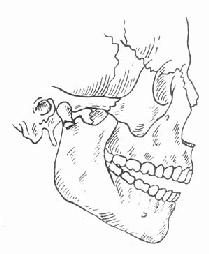

下颌骨骨折段的移位,主要是因肌肉牵拉所致。颏孔部骨折时,前骨折段常因降颌肌群的牵拉而向下移位,后骨折段常因升颌肌群的牵拉而向上移位(图4-14)。颏部的粉碎性骨折,中部骨折段由于颏舌肌、颏舌骨肌牵拉而向后移位。两侧骨折段由于下颌舌骨肌、舌骨舌肌的牵拉向中线移位,使下颌骨前部弓形变窄。这种骨折可引起舌后坠而发生呼吸困难,甚至发生窒息,应特别注意。髁状突骨折,多因间接受力所致,可与颏部骨折同时发生,应注意检查以免漏诊。髁状突骨折后,常因翼外肌的牵拉,向前内方移位,同时下颌升支因升颌肌群牵拉而向上移位,出现前牙不能闭合的状态。如双侧髁状突骨折,则前牙开牙合更明显(图4-15)。

| 图4-14 颏孔部骨折后骨折段移位情况 | 图4-15 髁状突骨折后骨折段的移位 |